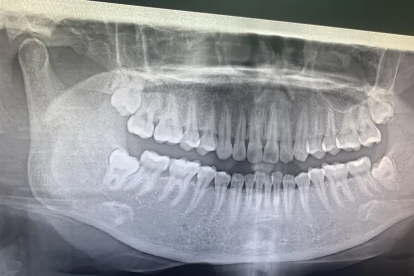

当智齿存在横向阻生、反复冠周炎发作或邻牙龋坏时,建议在炎症控制后1-2周拔除。但若患者有严重凝血功能障碍、未控制的高血压或妊娠期,需暂缓手术。拔牙前需拍摄口腔全景片评估牙根与下颌神经管关系,采用微创拔牙术减少骨组织损伤,术后24小时内禁止漱口以防血凝块脱落。